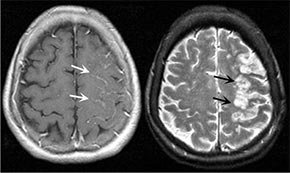

Brain

"Hipertónia esetén a magas levegő hőmérséklet a szív- és érrendszer komoly megterheléséhez és a szervezet összes rendszerének zavarához vezet. Az erek túlterheltek és nem birkóznak meg feladatukkal, a vérnyomás megemelkedik, nő a szívroham és a stroke kockázata"